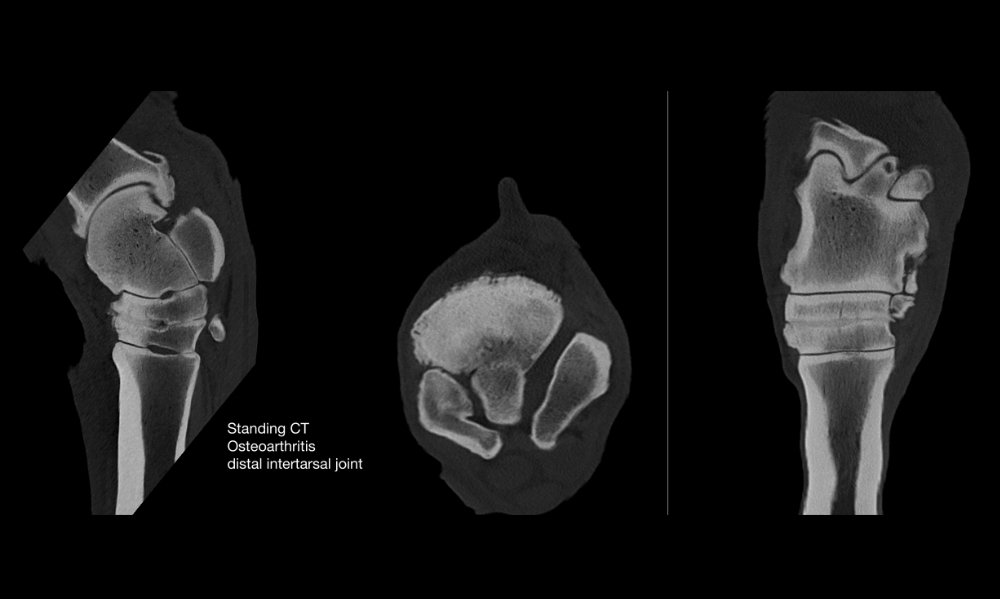

Distal Limb of the Standing Horse

Examinations up to the radius or the tibia

Incredibly short examination times as quick as 0.28 sec/16 cm (system dependent)

Superior soft tissue detection compared to low-field MRI

Positioning of the horse is similar to farrier services, providing familiarity and comfort

Standing, yet non weight bearing examinations allow CT arthrography without general anesthesia and reduce artifacts from load bearing

The 0.5mm slice size combined with the latest algorithms and over 80 reconstruction filters allow imaging of the smallest lesions in ligaments, tendons, and hyaline cartilage